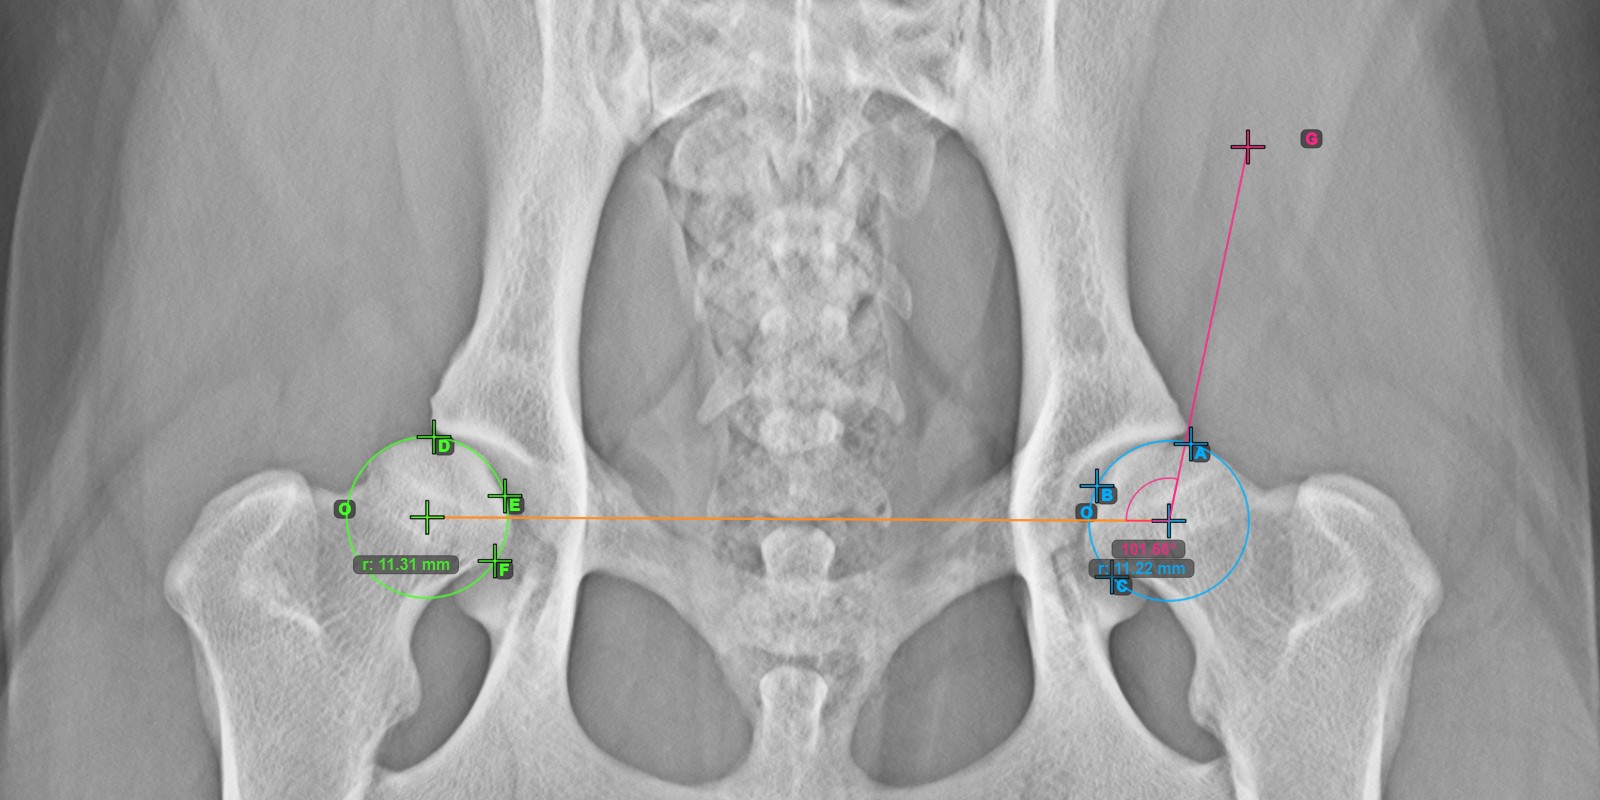

Calculate the left Norberg Angle measurement by marking a line on the effective edge of the left Acetabularis bone.

Mark a point near the left Caput Femoris and drag it along the effective edge of the left Acetabularis bone, forming the terminal side of the left Norberg Angle.

The drawn line must be a tangent to the effective edge of the left Acetabularis bone. The value and arc of the angle is automatically calculated.

The image below depicts the typical placement of the line and the calculated Norberg Angle measurement.